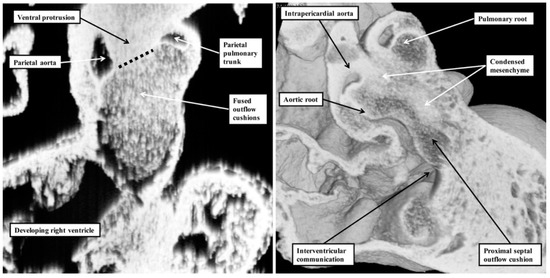

It is the lack of any “outlet septum” in the normal heart that is directly relevant to the appropriate change in terminology from “aortopulmonary septal complex” to “outflow tract septal complex” as proposed by Poelmann and Gittenberger-de Groot [1]. Our investigation of datasets prepared from developing mice reveals that the real aortopulmonary septum separates only the intrapericardial arterial trunks (Figure 6).

Figure 6. These images show the changes occurring in the separation of the outflow tract into its pulmonary and aortic components in the developing mouse. The left-hand panel shows the arrangement at embryonic day 11.5. The ventral protrusion from the dorsal wall of the aortic sac is separating the distal part of the outflow tract into its aortic and pulmonary components. At this stage of development, it is a true aortopulmonary septum. It is the major outflow cushions that are separating the intermediate and proximal components of the outflow tract. The right-hand panel shows the arrangement at embryonic day 12.5. By this stage, the distal outflow tract has been divided into the intrapericardial arterial trunks. By this stage, each arterial trunk has its own walls. Only the intrapericardial aorta is seen in this image. The major cushions have fused to separate the intermediate part of the outflow tract into the arterial roots. The proximal parts of the major cushions, however, have still to fuse. They will eventually separate the ventricular outflow tracts. Note the presence of the column of condensed mesenchyme extending into the proximal part of the septal outflow cushion. Said to be part of the “aortopulmonary septal complex”, the columns of condensed mesenchyme play no part in separating the intrapericardial components of the arterial trunks. Instead, they are key to separating the developing arterial roots and ventricular outflow tracts. As was indicated by Poelmann and Gittenberger-de Groot [1], it is more appropriate to describe the combined structures as the “outflow tract septal complex”.